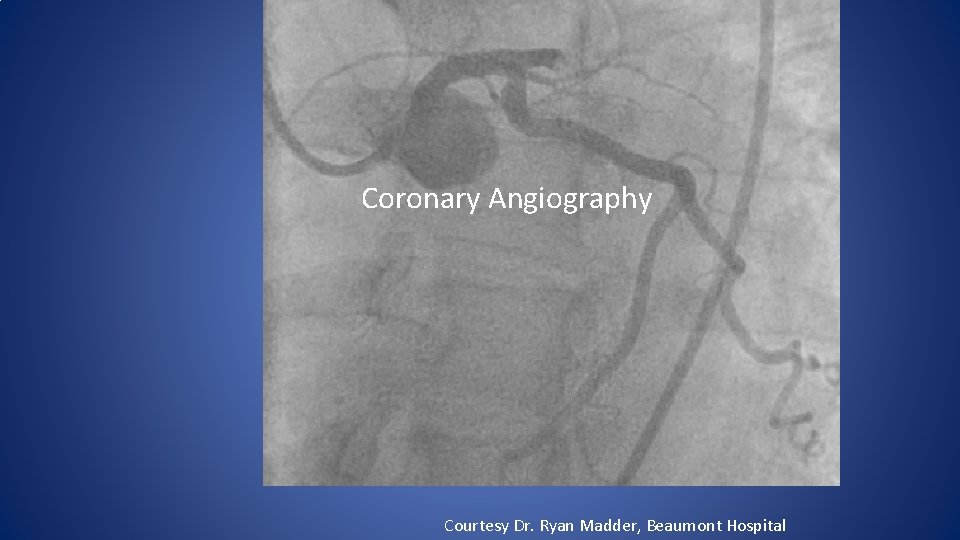

In March, 2009, 11 months after CTA Patient calls EMS due to sudden onset chest pain radiating to left arm. Courtesy Dr. Ryan Madder, Beaumont Hospital

Coronary Angiography Courtesy Dr. Ryan Madder, Beaumont Hospital

Courtesy Dr. Ryan Madder, Beaumont Hospital